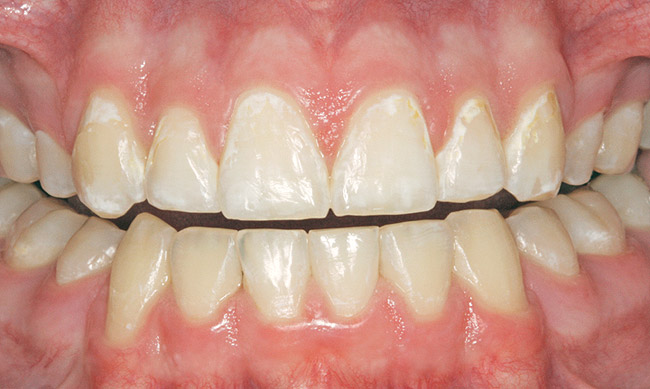

Caries infiltration is indicated for all age groups, up to the first third of dentin (D-1) (Figure 2). It is especially advantageous in interproximal areas, where a relatively large ratio of healthy hard tissue must be removed to eliminate carious tissue. Infiltration replaces hard tissue lost due to demineralization (to a maximum of 800 µm) with a low-viscosity resin, creating a barrier to further diffusion of carbohydrates and organic acids within the hard tissue, not on the tooth surface. This barrier stabilizes and effectively blocks the caries without changing the anatomic shape or appearance of the tooth.85 Additionally, treated lesions lose their whitish opaque color and blend with surrounding natural enamel, which is especially esthetic in the smooth surface type of lesions often found when fixed orthodontic appliances are removed (Figure 3 and Figure 4).

Figure 3  White spot lesions evident after orthodontic therapy (photograph courtesy of S. Paris and H. Meyer-Lueckel).

Figure 3

Figure 4  White spot lesions are imperceptible, blending with natural tooth color, after caries infiltration therapy (photograph courtesy of S. Paris and H. Meyer-Lueckel).

Figure 4